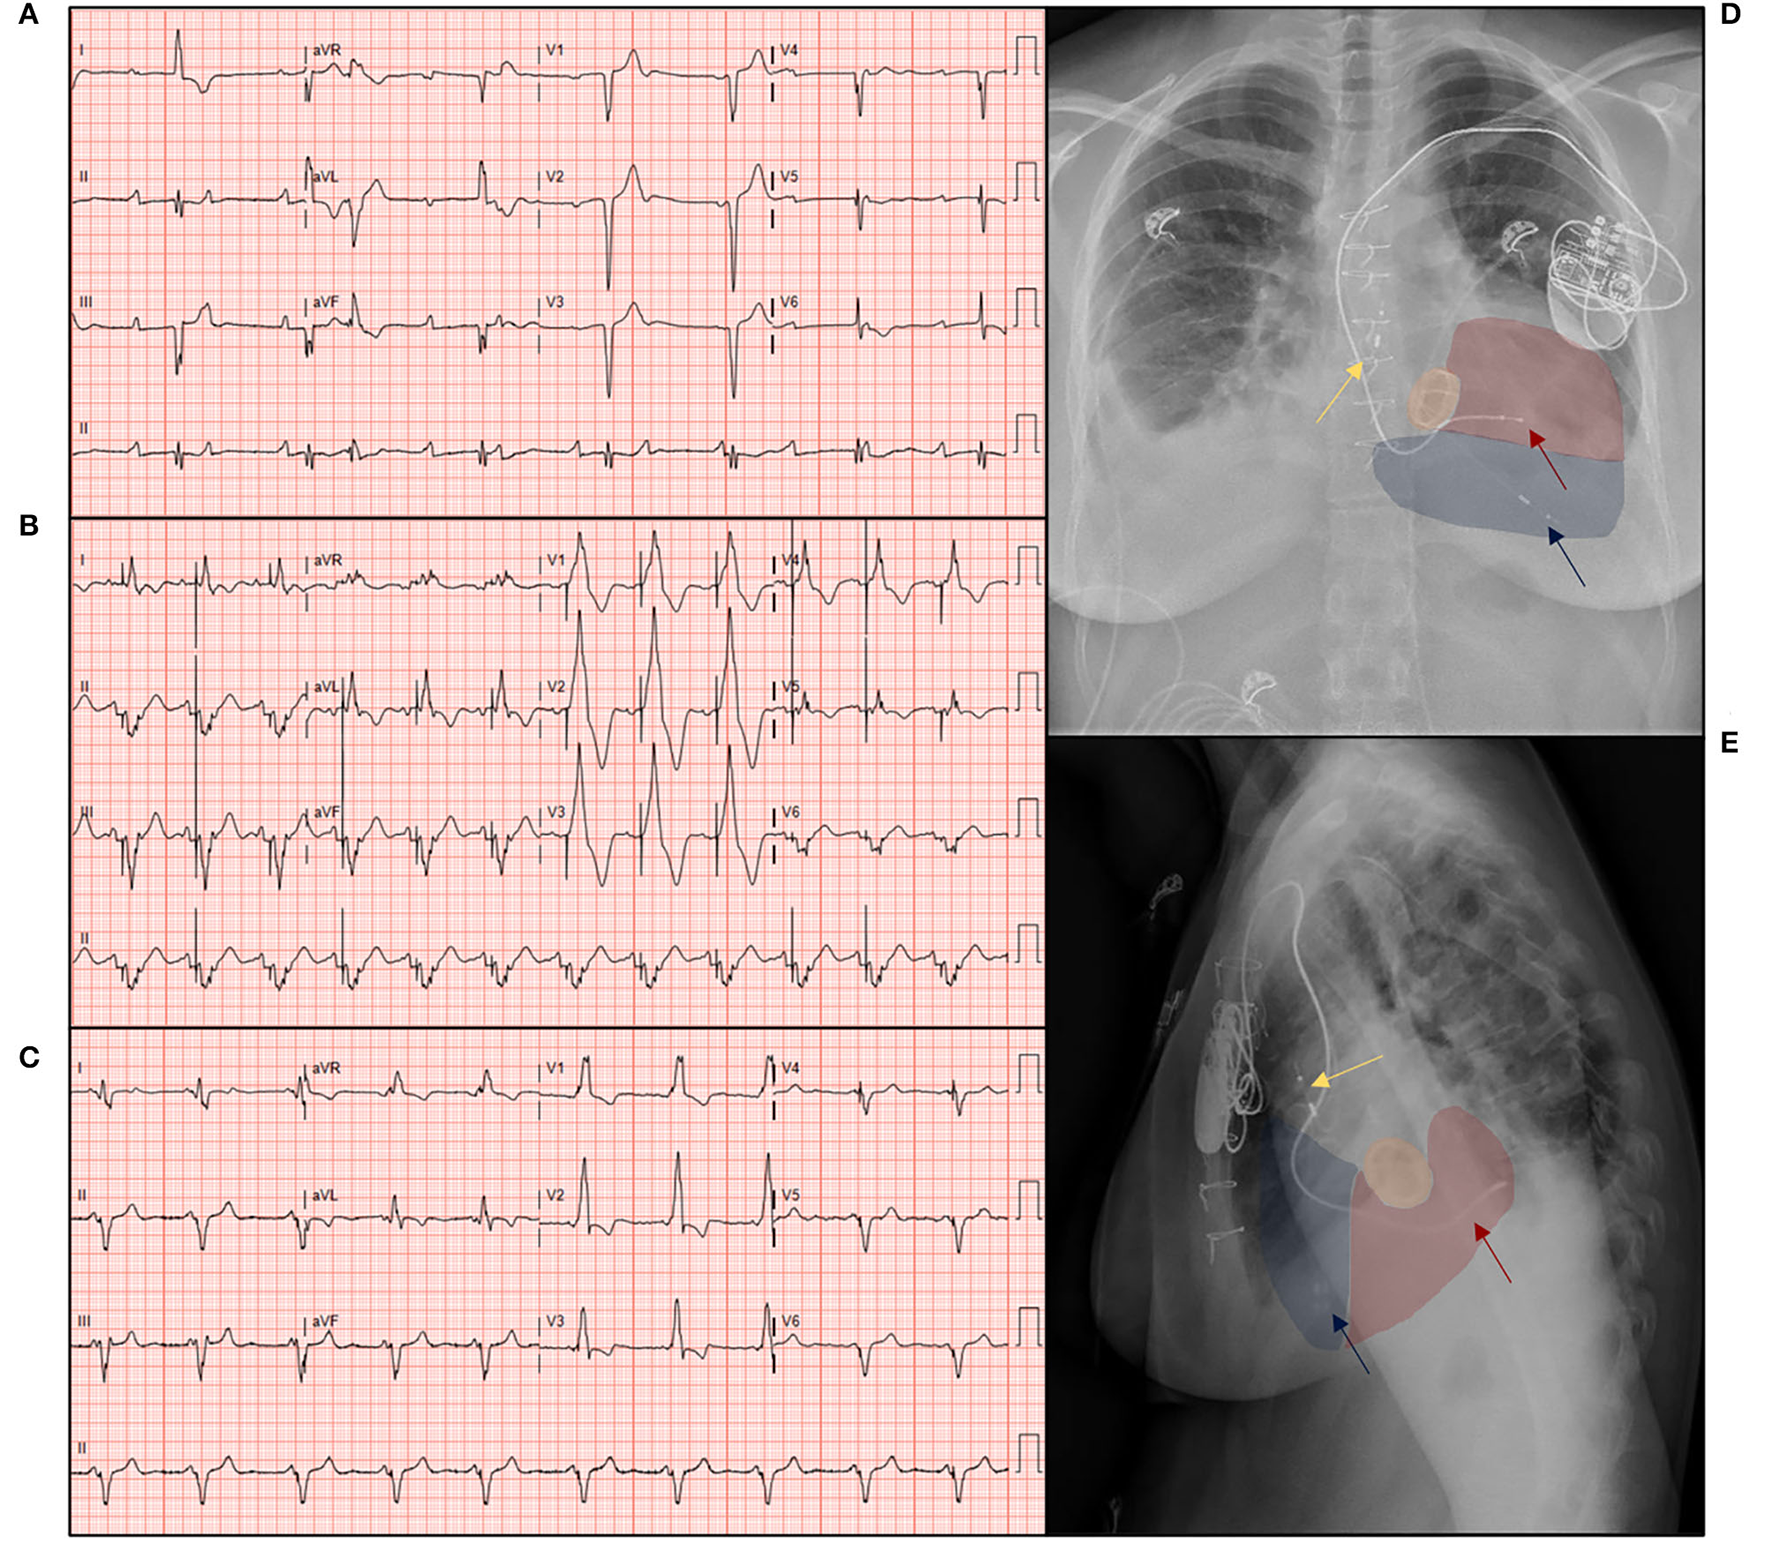

The primary outcome was the incidence and timing of high degree AV-block necessitating ventricular pacing. Chronic ventricular pacing was defined as > 40% subpulmonary left ventricular (LV) pacing, in accordance with the current ESC guidelines (2). Secondary outcomes consisted of clinical outcomes, such as the composite clinical endpoint of progressive heart failure (all-cause mortality, VAD implantation/heart transplantation, and implantation/upgrade to CRT). A representative example of the electrocardiographic effects of LV and CRT pacing modalities in a ccTGA patient with a high-degree AV-block is shown in Figure 1. The first event per patient was taken for analysis, and functional clinical parameters [such as, New York heart association (NYHA) functional class, pharmacological therapy, ECG parameters, laboratory findings, including biomarker N-terminal-pro hormone B-type natriuretic peptide (NT pro-BNP), and echocardiographic parameters] were collected at that point. All patient data were described, as well as a comparative analysis between patients with chronic LV pacing and patients with native AV-conduction. Patients with CRT prior to or concomitant during TV surgery were excluded from the comparison between clinical outcomes at the last follow-up and the incidence of the composite endpoint.

Figure 1

The 12-lead ECG recordings and chest X-rays of a patient with congenitally corrected transposition of the great arteries, illustrating the effects of subpulmonary ventricular pacing, and cardiac resynchronization therapy on an electrocardiogram (ECG). The 12-lead ECG with (A) sinus rhythm and a total atrioventricular (AV)-block with ventricular/junctional escape rate of 48/min; (B) sequential subpulmonary left ventricular pacing of 75/min, note the broad paced QRS complex of 245 ms; (C) biventricular pacing after upgrade to a cardiac resynchronization therapy (CRT), note the reduction of QRS duration to 137 ms, illustrative of the electrical contribution of the systemic right ventricular (sRV) activation. (D) Postero-anterior, (E) lateral chest X-ray showing the pacing lead in the coronary sinus (red arrow) in the systemic right ventricle (red), atrial lead in the right atrium (yellow arrow), and transvenous pacing and ICD leads (blue arrow) in the subpulmonary left ventricle (LV) (blue), note the mechanical tricuspid valve in situ (orange).